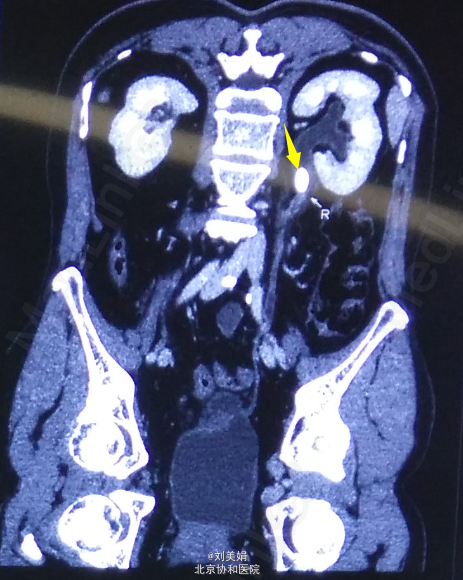

主 诉:体检发现右肾结石8个月 现病史:患者2014-11体检超声发现右肾结石,未予特殊诊治。2015-03因“类风湿性关节炎”入住我院普通内科,期间查泌尿系超声:右侧输尿管上段宽0.7cm,内见条状强回声,长约1.8cm,后伴声影,右侧输尿管中下段显示欠清。考虑右输尿管上段结石伴输尿管稍扩张,右肾盂分离。行CTU检查:右肾盂-输尿管连接处(UPJ)见类圆形密度增高影,大小约15mm×10mm,平扫CT值约1255Hu,其近端输尿管及右肾盂肾盏轻度扩张积水,壁略增厚毛糙,病灶周围见多发索条影。 小便夜尿增多,3-5次/晚,一年体重下降3kg。 右肾区轻度叩击痛,右输尿管走行区轻度压痛。

泌尿系结石双能量CT+成分分析:右输尿管-肾盂连接处(UPJ)见类圆形高密度影,大小约13mm×10mm,CT值约1049Hu,其近端输尿管及右肾盂肾盏扩张积水,输尿管及肾盂壁略增厚毛糙,病变周围多发索条影。左侧肾盂肾盏及输尿管未见明显异常。前列腺增大伴钙化灶。 泌尿系结石双能量成分分析:右UPJ结石主要成分为草酸盐。